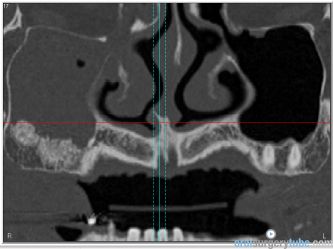

Con este comentario haremos una pausa en el caso hasta que llegue la colocación de los implantes. Por el momento, está todo solucionado. No hay sintomatología alguna, y lo más importante, en TAC realizado el martes 31.07.2018, podemos ver que el seno ha drenado por completo y está aireado. Hasta nuevo aviso, suspendemos todo tipo de medicación. Subimos imágenes del último TAC donde podemos apreciar que hemos perdido algo de xenoinjerto, pero la zona de menor altura aún tiene 10 mm. Podemos ver en una de las imágenes la zona de la ventana por donde el seno drenaba. Esperaremos el tiempo reglamentario para poder reevaluar si el xenoinjerto sigue siendo viable. Ha sido un gran placer contar con este equipo y poder aportar un grano de arena a solucionar complicaciones quirúrgicas.

Continúo con el seguimiento que vamos dando a este paciente: Visitado el miércoles 11.07.2018. Hay ausencia total de sintmatología. Retiramos el drenaje, hacemos Prueba de Valsalva positiva, pero sale aire y un poco de sangre. Dejamos cicatrizar por segunda intención. Pedimos continuar la medicación antibiótica y solicitamos un TAC. El seno maxilar está ocupado como vemos en la imagen, pero el biomaterial está contenido en la zona injertada: no existe ningún gránulo de xenoinjerto dentro del seno. La apófisis mastoidea está aireada.